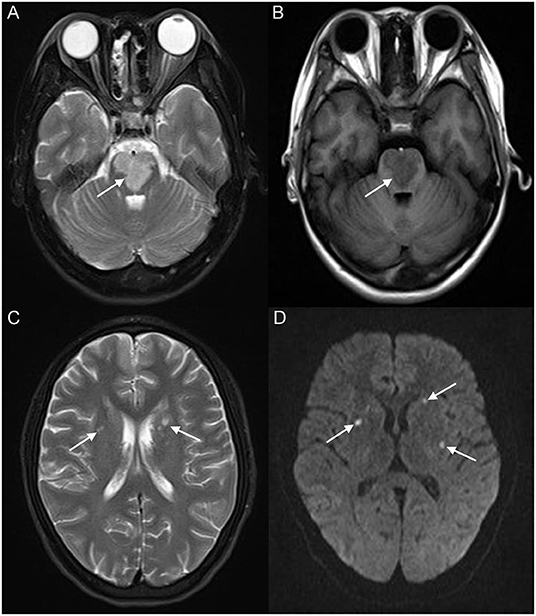

A 17-year-old girl presented to our hospital on August 22, 2021 with clouding of consciousness for more than 3 days. At 3+days prior, the patient was unable to speak the patient was unable to speak when called softly and unable to open the right eye, combined with involuntary movements of the limbs and incontinence. The patient visited the local hospital immediately, where relevant tests were performed, suggesting intracranial lesions. Since the specific treatment measures were unavailable at the previous hospital, she was transferred to our hospital for further treatment. There was no history of trauma or familial genetic diseases, such as high blood pressure and diabetes. Physical examination revealed a body temperature of 37.0°C, heart rate of 110 bpm, regular heart rhythm, blood pressure of 113/77 mmHg, and no pathological murmurs in the valve region; pulmonary auscultation revealed coarse rales in the entire lung. The pupils were equal, round, and pupillary light reflexes were delayed. Both lower limbs exhibited hypertonia and hyperreflexia of the knee and tendon reflexes. Laboratory examinations revealed the following levels (normal range): coagulation function test showed D-dimer was 0.57 mg/L (< 0.5 mg/L) and fibrinogen was 5.82 g/L (2.00–4.00 g/L). Routine blood tests showed that the absolute value of neutrophils was 7.38 × 109/L (1.8 × 109/L−6.3 × 109/L). Infection-related markers showed that the hypersensitive C-reactive protein level was 111.563 mg/L (0.068–8.200 mg/L). Creatine kinase, α-hydroxybutyrate dehydrogenase, and lactate dehydrogenase levels were 148 U/L (26–140 U/L), 218 U/L (90–180 U/L), and 295 U/L (140–271 U/L), respectively. Computed tomography pulmonary angiography (CTPA) detected filling defects in the right atrium, left atrium, and left lower pulmonary basilar artery (Figure 1), and a diagnosis of Pulmonary embolism was made. Transthoracic echocardiography (TTE) revealed irregular iso-echoic masses in the bilateral atrium that were likely myxomas, given their location and appearance in a young patient; the myxoma in the left atrium measured approximately 38 × 21 mm, and it was attached to the junction of the lower part of the interatrial septum (IAS) and the root of the anterior mitral leaflet; in the right atrium it measured approximately 51 × 27 mm, and it was attached to the lower part of the IAS (Figure 2A). These masses resulted in the acceleration of the tricuspid valve antegrade flow (Figure 2B). Craniocerebral computed tomography (CT) showed extensive hypodensity in the bilateral parts of the pons and patchy hypodensity in the left corona radiata area and bilateral basal ganglia areas. Magnetic resonance imaging (MRI) also revealed extensive hypointensity on T1-weighted imaging and hyperintensity on T2-weighted imaging in the bilateral parts of the pons, and a patchy hyperintensity on T2-weighted imaging in the bilateral basal ganglia areas; bilateral centrum semiovale; and right frontoparietal lobe, which presented as high signal on diffusion-weighted imaging (DWI) (Figure 3). This confirmed the diagnosis of brain ischemia. To prevent thrombosis, low molecular weight heparin calcium (subcutaneous injection, 0.4 ml/12 h) was commenced on the second day of admission and continued until discharge. The patient underwent successful removal surgery for a biatrial myxoma. The masses were sent for histological examination, which confirmed the presence of a myxomatous matrix containing myxoma cells (Figure 4). The patient recovered uneventfully and was discharged 9 days after the procedure. The patient has been followed-up postoperatively for over 2.5 months, and limb motor function of the patient has recovered to some degree, but there is intellectual and cognitive decline.

Figure 3. Brain magnetic resonance imaging (MRI) revealed extensive hyperintensity on T2-weighted imaging and hypointensity on T1-weighted imaging of the bilateral parts of the pons (white arrow) (A,B); a patchy hyperintensity on T2-weighted imaging of the bilateral basal ganglia, bilateral centrum semiovale (white arrow) (C), and right frontoparietal lobe, which presented a high signal on diffusion-weighted imaging (DWI) (white arrow) (D).

Cardiac myxoma may cause embolic events during tumor tissue shedding, and cases of obstruction are relatively common in cardiac myxomas, and the morbidity rate of embolism is approximately 30–40% (14). Neurologic events are the most common embolic events followed by systemic embolic events, typically occurring at a rate of 42 and 29%, respectively. However, pulmonary embolic events are rare (15). Pulmonary embolism and cerebral stroke are uncommon but extremely significant complications of cardiac myxoma, with the risk of embolic events in cases of cardiac myxoma associated with the mass's appearance; typically, villous myxomas are more likely to cause embolism (16). Acute embolic stroke occurs when shedding tumor tissue reaches the cerebrovascular system, and it is often associated with high rates of mortality and disability, which poses a great risk to the life of the patients. Atrial myxomas have become a potential source of emboli; therefore, the primary presentation of many patients with a clinical history of myxomas is stroke (17, 18). In our case, the primary reason for the patient to go to the hospital for treatment was unconsciousness. Brain MRI revealed territorial cerebral infarction in the bilateral parts of the pons and small area cerebral infarction in the bilateral basal ganglia areas, bilateral centrum semiovale, and right frontoparietal lobe.